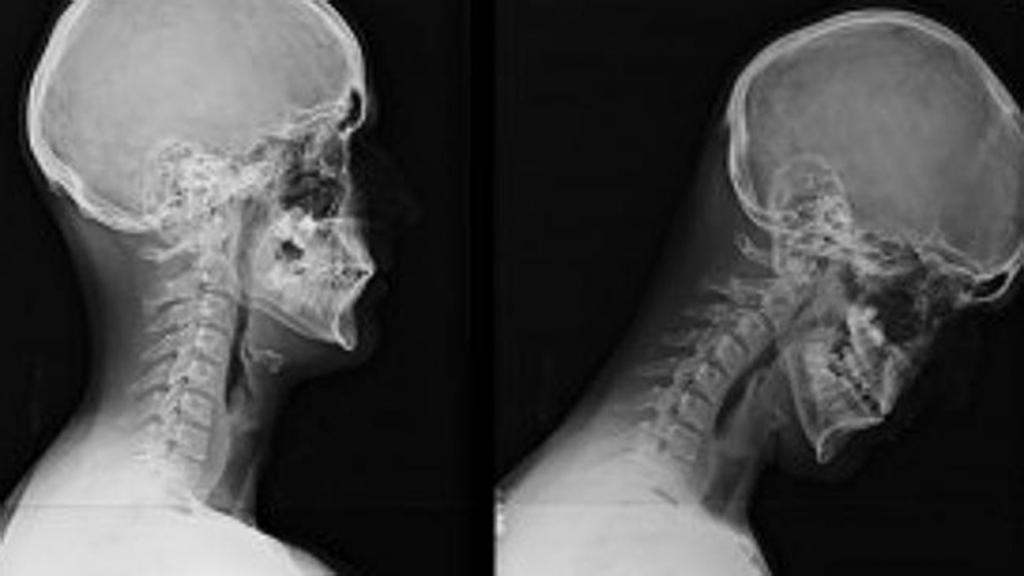

Если болит шея сзади у основания головы — следует обратиться за консультацией к неврологу. Самостоятельно выяснить причины дискомфорта невозможно. Для диагностики шейного спондилеза назначают:

- КТ (компьютерная томография) позвоночника, при помощи которой можно детально рассмотреть все плотные структуры шеи.

- МРТ позвоночника для оценки состояния мягких тканей.

- рентген шейного отдела позвоночника позволит рассмотреть степень искривления и патологии позвонков;